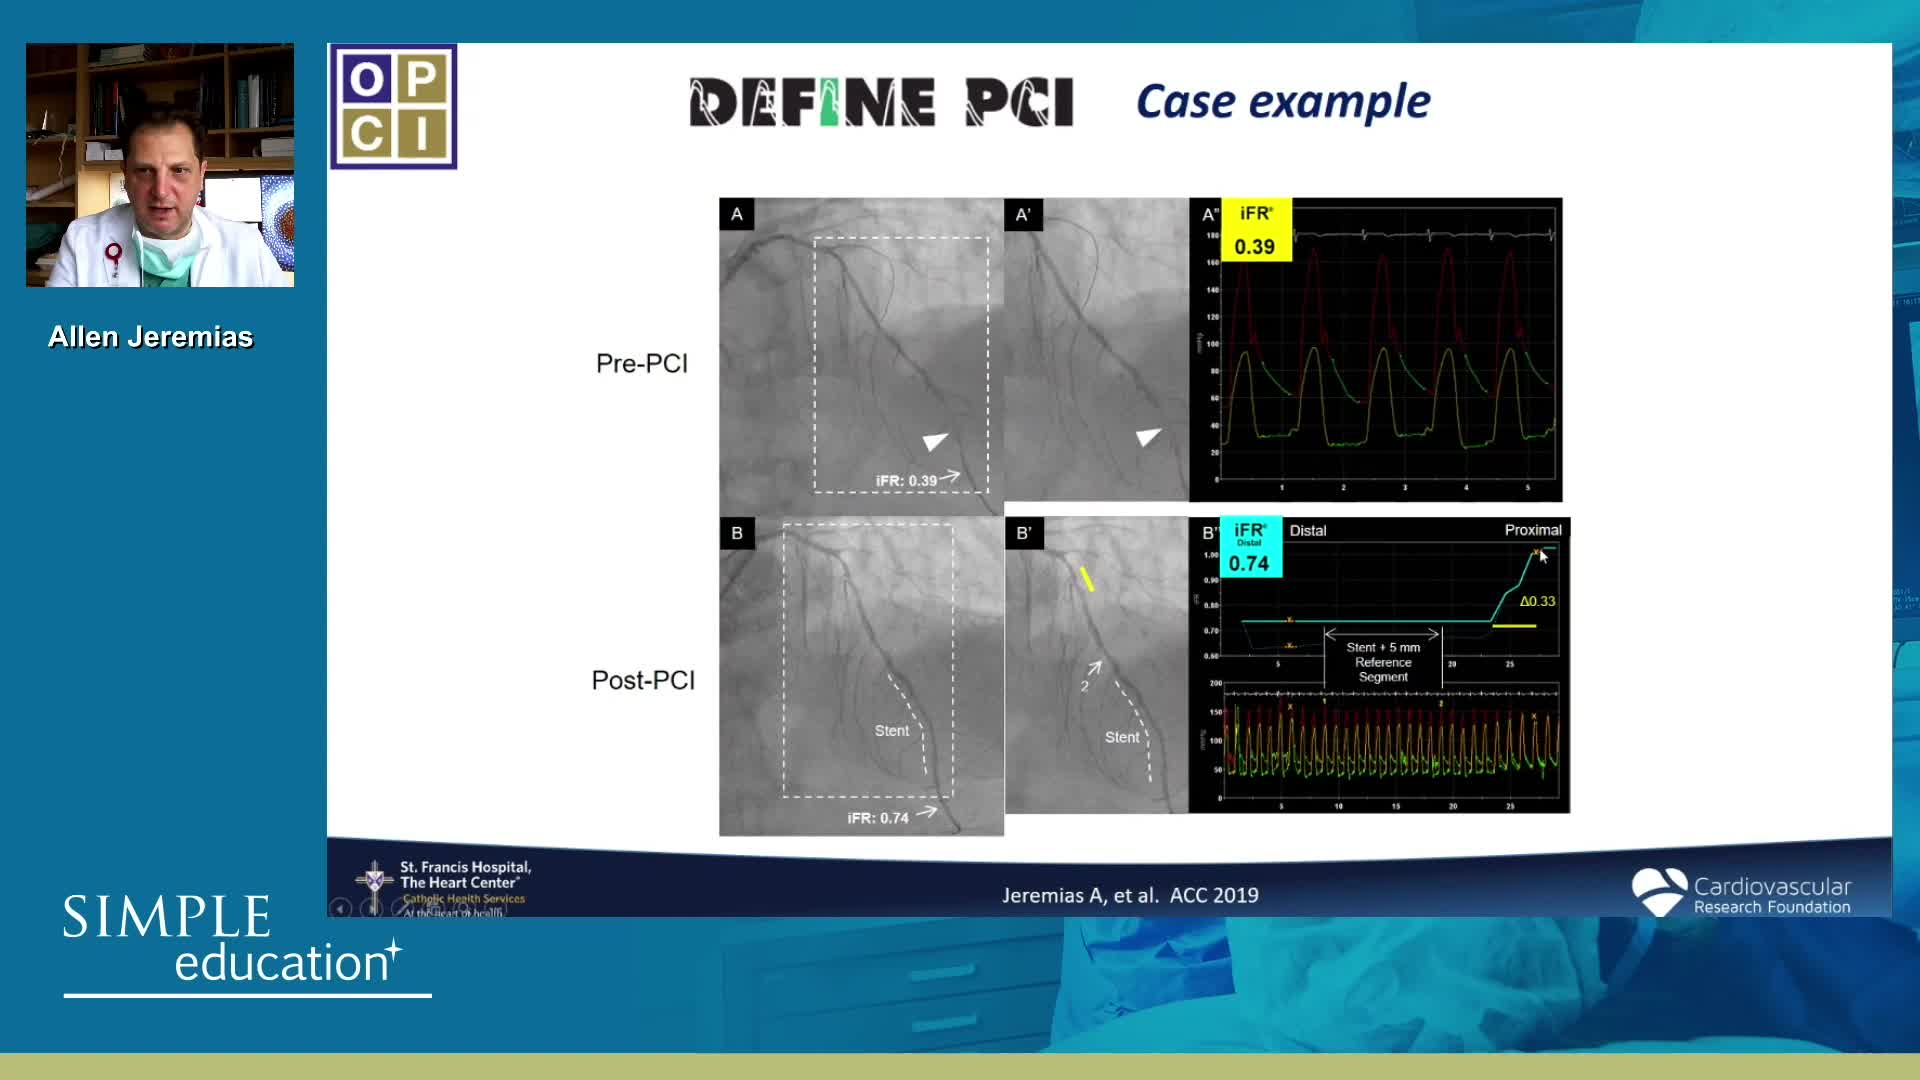

Essential steps for physiology-based PCI planning and guidance - Dr Allen Jeremias

Coronary physiology gate keeper or guide to coronary PCI? Rationale and design of DEFINE-GPS

DEFINE-GPS Leading to Full Integration of Coronary Physiology to PCI Decision-Making